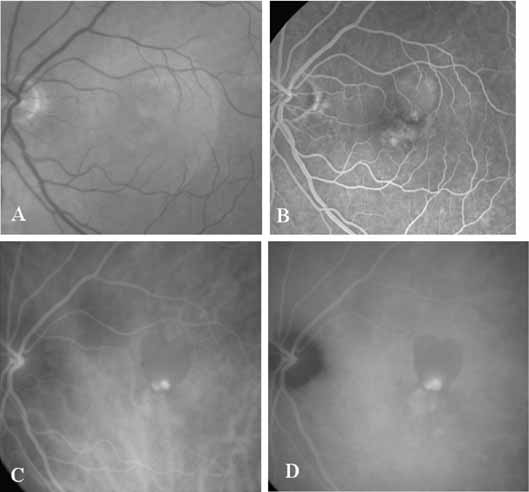

Unlike fluorescein angiography, however, ICG angiographic studies have pointed out that certain principles of laser photocoagulation treatment may not hold with this new imaging capability. This is particularly true with the concept that all areas of CNV need to be obliterated to achieve a successful anatomic result. A careful evaluation of ICG angiograms in some patients with occult CNV has revealed that two forms of neovascular lesions may exist: (1) localized, intensely hyperfluorescent leaking areas of “active” CNV; and (2) more subtle and larger areas of hyperfluorescence with minimal leakage, representing “quiescent” portions of the neovascular complex (Fig. 8). A pilot study by Guyer and colleagues22 demonstrated that localized photocoagulation treatment applied to the active area of CNV alone might result in successful and long-term anatomic stabilization and improvement in the visual acuity in some patients (Fig. 9). A subsequent review of these lesions has demonstrated that they may represent a subpopulation of occult CNV known as polypoidal choroidal neovascularization, described later.

Flower revealed that feeder vessels (FVs) identified by dynamic ICG angiography, but not by FA, may be amenable to treatment with argon green laser.32 ICG angiography is then performed at regular intervals after treatment to determine the treatment response. A second laser treatment is administered if ICG angiography reveals a patent FV. A 40% success rate was found, initially, with a more recent report of 75% success.33 It appears that dynamic ICG angiography, especially high-speed ICG, detects smaller FVs and can therefore be used in treatment of these vessels. (Fig. 10)

ICG angiography has clearly provided new and important diagnostic information, identifying well-defined, potentially laser-treatable lesions in approximately 30% of occult cases.21,30 In addition, the successful elimination of the exudation in patients with occult CNV by obliteration of the hyperfluorescent lesion with laser photocoagulation treatment suggests that ICG-guided laser treatment of occult CNV may be a useful technique in the management of some of these difficult cases (Fig. 13).